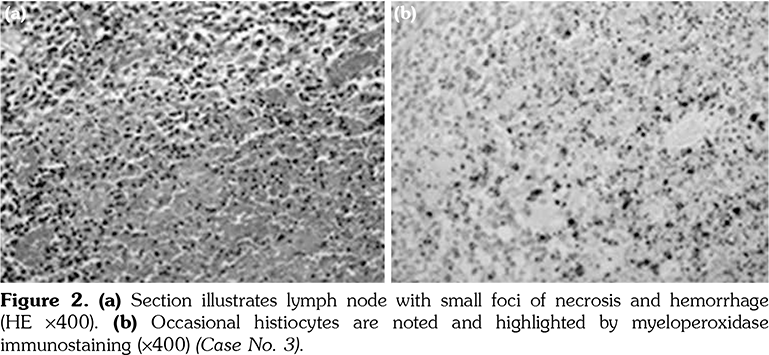

Diagnosis of KFD depends upon presence of appropriate histopathology of the lymph node (LN), which typically shows paracortical well-circumscribed necrotic lesions consisting of karyorrhexis, fibrin deposits, abundant CD68 plasmacytoid monocytes and infiltration of histiocytes in absence of plasma cells or neutrophils.[2-5]

The excised cervical LNs of the 11 patients showed variable degrees of necrotizing lymphadenitis with foci of necrosis surrounded by histiocytes that are positive for CD68 and myeloperoxidase. The histopathology of the excised LN for patients numbered 2, 3, and 7 is illustrated in Figures 1, 2 and 3, respectively.